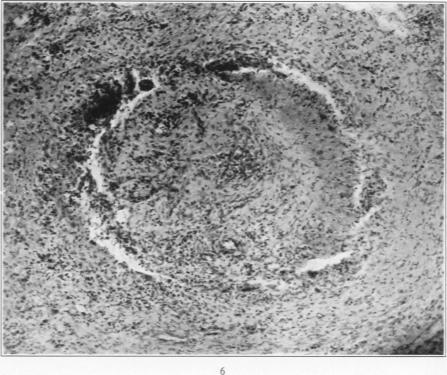

Polyarteritis nodosa: Report of case.

Am J Pathol. 1939 Jan;15(1):79-88.5.